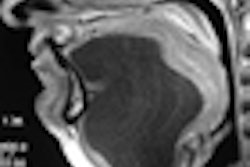

Researchers at the Greater Poland Medical Centre in Poznan conducted a retrospective study of patients treated for head and neck squamous cell carcinoma to compare the diagnostic performance of PET/CT and ultrasound, as well as their combined use to detect local recurrence. Their objective was to determine the effectiveness of the examinations with respect to identifying cancer in patients whose clinical otolaryngological exams did not reveal any sign of cancer recurrence.

Lead author Dr. Malgorzata Wierzbicka, of the department of otolaryngology of Poznan University of Medical Sciences, and colleagues relied on lymph node size and shape criteria to determine abnormalities, whereas PET/CT provided additional information about metabolism and precise localization of the occult recurrence.

"Ultrasound offers numerous advantages over PET/CT," the authors wrote. "It is less time-consuming, inexpensive, repeatable, well-tolerated by patients, and does not expose a patient to radiation." They noted that its disadvantages were interobserver variability and the fact that imaging was limited to soft tissue.